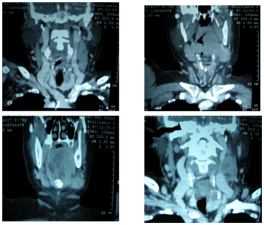

A 71 year old female patient with history of chronic smoking, type 2 diabetes mellitus and arterial hypertension, presented with a white nodular painful mass on the left lateral side of the tongue of one month of duration. She had been treated with mouth washes, antibiotics and antimycotics with no improvement. Two weeks later she noticed aslow-growing, non-painful tumoron the left side of the neck. Physical examination revealed limitation of the oral opening dueto pain and a very painful tumor on the Left part of the Tongue fixed to the floor of the mouth (Figure 1). On the neck an enlarged thyroid was palpated with predominance of the left lobe and a second level node of 3cm, indurated and fixed to the under lyingt issue. Three weeks after the primary evaluation, she presented with increased volume of the tongue tumor, involving submental region and both submandibular triangles with predominance of the left one. Computed tomography showed an hypodense tumor on the left side of the tongue, heterogenouse lymph node on the second left level of the neck and a hypodense mass in the left lobe of the thyroid with calcifications on the inside. She was admitted for an incisional biopsy of the tongue tumor, and fine-needle aspiration cytology (FNAC) of the node and thyroid tumor (Figure 2). Histopathologic report was a primary anaplastic thyroid carcinoma with tongue and neck metastases (Figure 3). The patient was sent to the National Cancer Institute of Mexico, where they only offered palliative care because she rejected any other therapeutic measures.

Figure 2 Histopathologic report of thyroid carcinoma with tongue and neck metastases.

Figure 3 Anaplistic thyroid carcinoma & lingual metastases of anaplastic thyroid carcinoma.